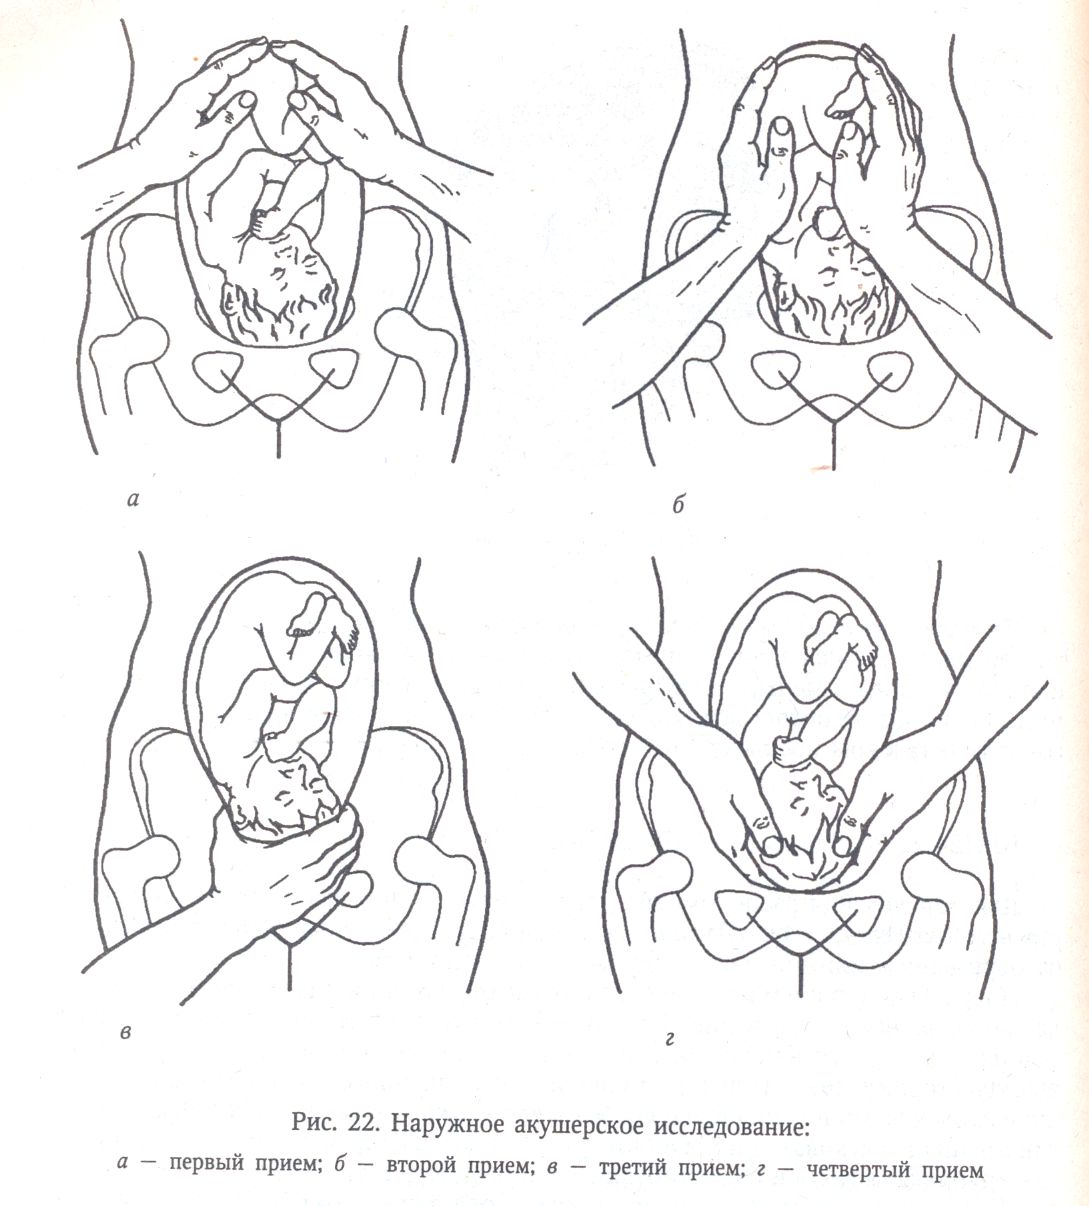

Наружное акушерское исследование приемы Леопольда Левицкого

Третий прием Леопольда-Левицкого

Приемы наружного акушерского исследования Леопольда Левицкого

Второй прием Леопольда-Левицкого определяет

Приемы наружного акушерского исследования Леопольда Левицкого